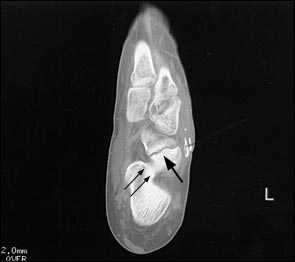

При выполнении КТ оптимально использовать малый шаг (1,5мм) и делать срезы в плоскости таранно-ладьевидного сустава. КТ часто позволяет выявить неполный перелом, начинающийся проксимально по тыльной поверхности и идущий в косом направлении к дистальной части подошвенной поверхности.

Большой стрелкой обозначен перелом ладьевидной кости, двумя маленькими стрелками – синостоз пяточной и ладьевидной кости.

На основании КТ-картины можно подразделить пациентов на 3 группы, 1 тип - изолированные переломы дорсальной кортикальной пластинки, 2 тип – перелом дорсального кортекса и тела кости, 3 тип – полный перелом ладьевидной кости. Тяжесть течения и сроки сращения увеличиваются соответственно от 1 типа к 3.